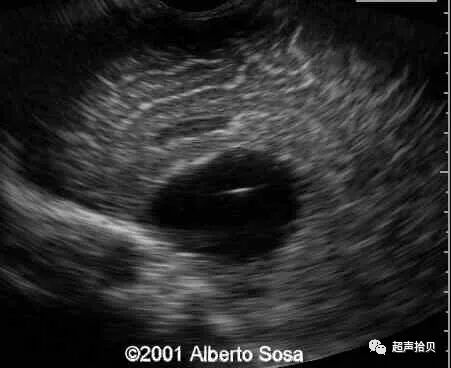

图3:位于颞窝的蛛网膜囊肿(C)。A:26周妊娠时横向超声扫查获得囊肿图像,彩色多普勒超声检查显示囊肿中没有流动。 B,28孕周产前核磁共振显示囊肿(C)位于颞侧窝(T2加权像[T2WI],横向平面)。 C,出生后1个月的产后MRI证实囊肿。(T2加权像[T2WI],横断面)